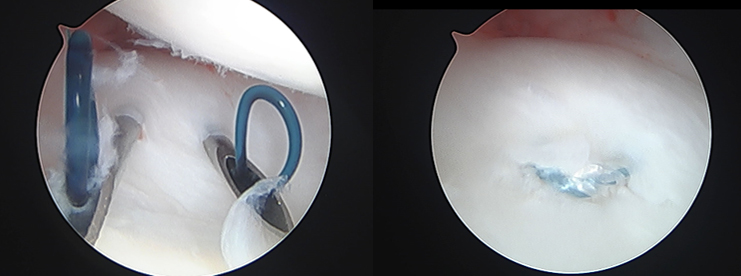

【関節鏡視下TFCC関節包縫合術】

手術は関節鏡視下TFCC縫合術(TFCC関節包縫合術、経骨孔TFCC縫合術)、手関節鏡視下デブリドマン、TFCC再建術、尺骨短縮骨切り術、鏡視下尺骨遠位端部分切除(Wafer procedure)などがあります。各術式は年齢、性別、利き手側、スポーツや活動レベル、受傷機転、罹病期間、症状、身体所見などの他、画像評価によるTFCCの状態や突き上げ症候群の有無、DRUJの状態など総合的に評価して決定していきます。手術後は3~6週間、外固定を行います。また、リハビリテーションを行います。状態次第ですが、術後3~6か月程度で日常生活動作やスポーツ復帰が可能となります。